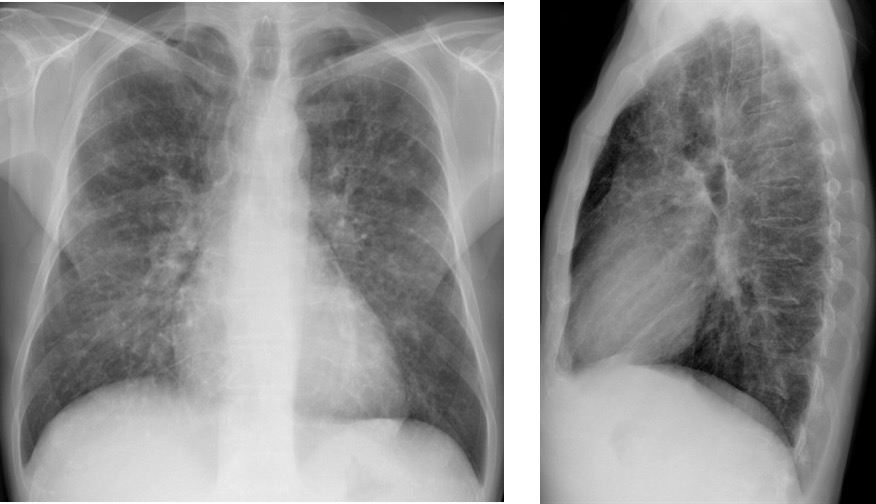

CASO: Febrícula y tos de 4 días de evolución.

Hallazgos:

- En la placa PA se observa una asimetría en los hilios pulmonares, el hilio izquierdo tiene una densidad aumentada.

- Tras examinar la placa lateral se observa un aumento de densidad en la columna que puede ser compatible con una condensación, es el signo de la desnificación vertebral.

SIGNO DE LA DENSIFICACIÓN VERTEBRAL: En la radiografía lateral normal, la densidad de la columna torácica tiende a disminuir desde la parte superior hasta el diafragma; la alteración de ese patrón por la presencia de una densidad superpuesta a la columna, indica la existencia de una consolidación pulmonar. Este signo adquiere especial valor cuando en la proyección posteroanterior la consolidación está oculta en el espacio retrocardíaco o en la base pulmonar.